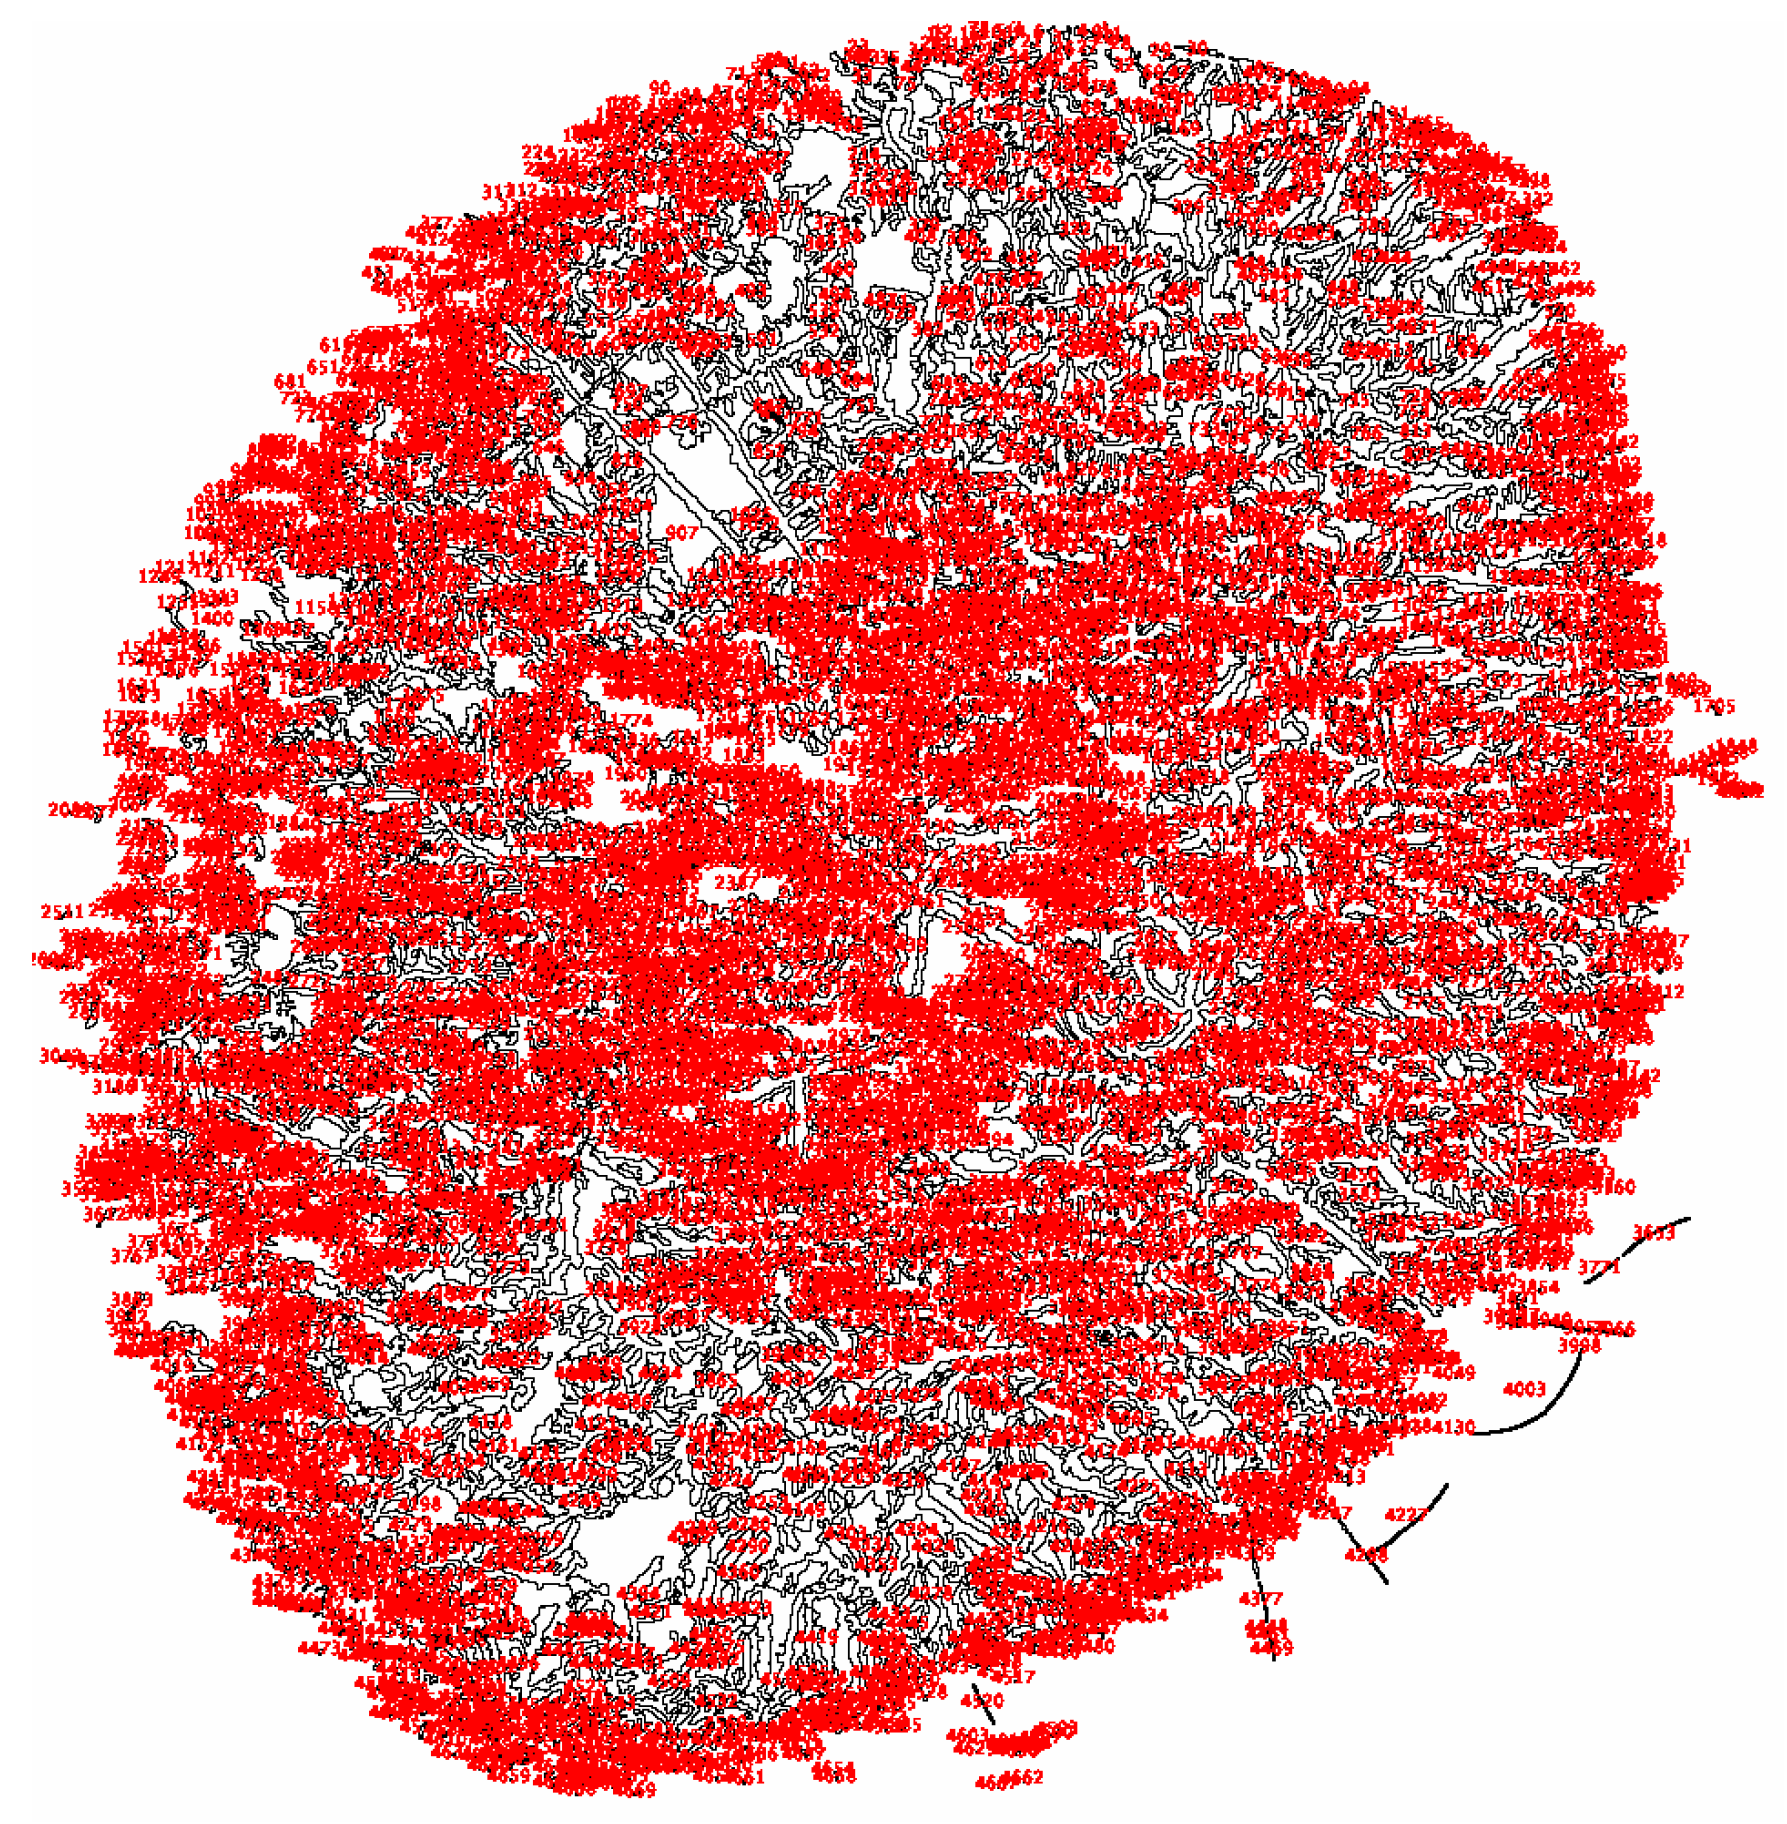

- Masmali, A.M.; Murphy, P.J.; Purslow, C. Development of a new grading scale for tear ferning. Contact Lens Anterior Eye 2014, 37, 178–184. [Google Scholar] [CrossRef]

- Masmali, A.M.; Purslow, C.; Murphy, P.J. The tear ferning test: A simple clinical technique to evaluate the ocular tear film. Clin. Exp. Optom. 2014, 97, 399–406. [Google Scholar] [CrossRef] [PubMed]

| Classification | S-DED Group (n = 10) | DED Group (n = 10) | Control Group (n = 10) | p-Value * | |||

| MASMALI | |||||||

| Grade 0 | 0 | 0.0 | 4 | 40.0 | 2 | 20.0 | 0.036 |

| Grade 1 | 3 | 30.0 | 3 | 30.0 | 6 | 60.0 | |

| Grade 2 | 7 | 70.0 | 3 | 30.0 | 2 | 20.0 | |

| ROLANDO | |||||||

| Normal | 3 | 30.0 | 7 | 70.0 | 8 | 80.0 | 0.040 |

| Pathologic | 7 | 70.0 | 3 | 30.0 | 2 | 20.0 | |